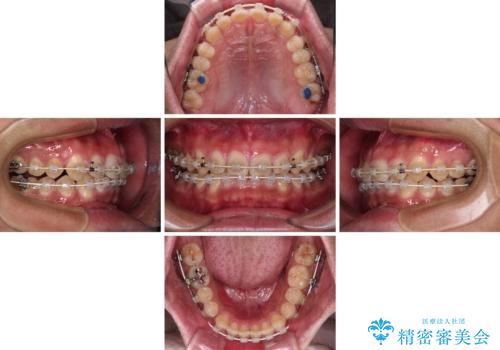

深い咬み合わせと隙間の空いた歯列をワイヤー矯正で改善

- 前歯の隙間と深い咬み合わせを改善したいとのことで来院された患者様です。

マウスピース矯正の自己管理が面倒とのことで、ワイヤー矯正により治療を行うこととしました。

奥歯の咬み合わせは理想的な状態であったため、ワイヤー矯正でもインビザラインでも比較的容易に対応可能でした。